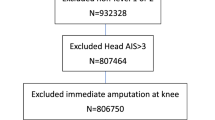

Between January 2006 and September 2011, 191 adult trauma patients presented to the Ryder Trauma Center, an urban level I trauma center in Miami, Florida with traumatic LEVIs. Among them 10 (5.2 %) patients were diagnosed with SACS and were included in this analysis. Institutional review board approval for this study was obtained, waiving the need for informed consent. Patients with concurrent intra-abdominal injury were excluded from this study. Data was retrospectively collected by a single investigator and included patient’s demographics, mechanism of injury, type of vascular injury, and physiologic status on initial assessment. Laboratory and clinical data evaluation included emergency department (ED) base deficit, serum pH, and hematocrit levels. The amount of crystalloids and colloids given during the operative fluid resuscitation phase was recorded. Injury severity was determined based on the Revised Trauma Score (RTS), Injury Severity Score (ISS), and admission Glasgow Coma Scale (GCS). A severe injury was categorically defined as an ISS of greater than 15. Outcome variables included mortality, surgical procedures, complications, hospital length of stay, and intensive care unit (ICU) length of stay.